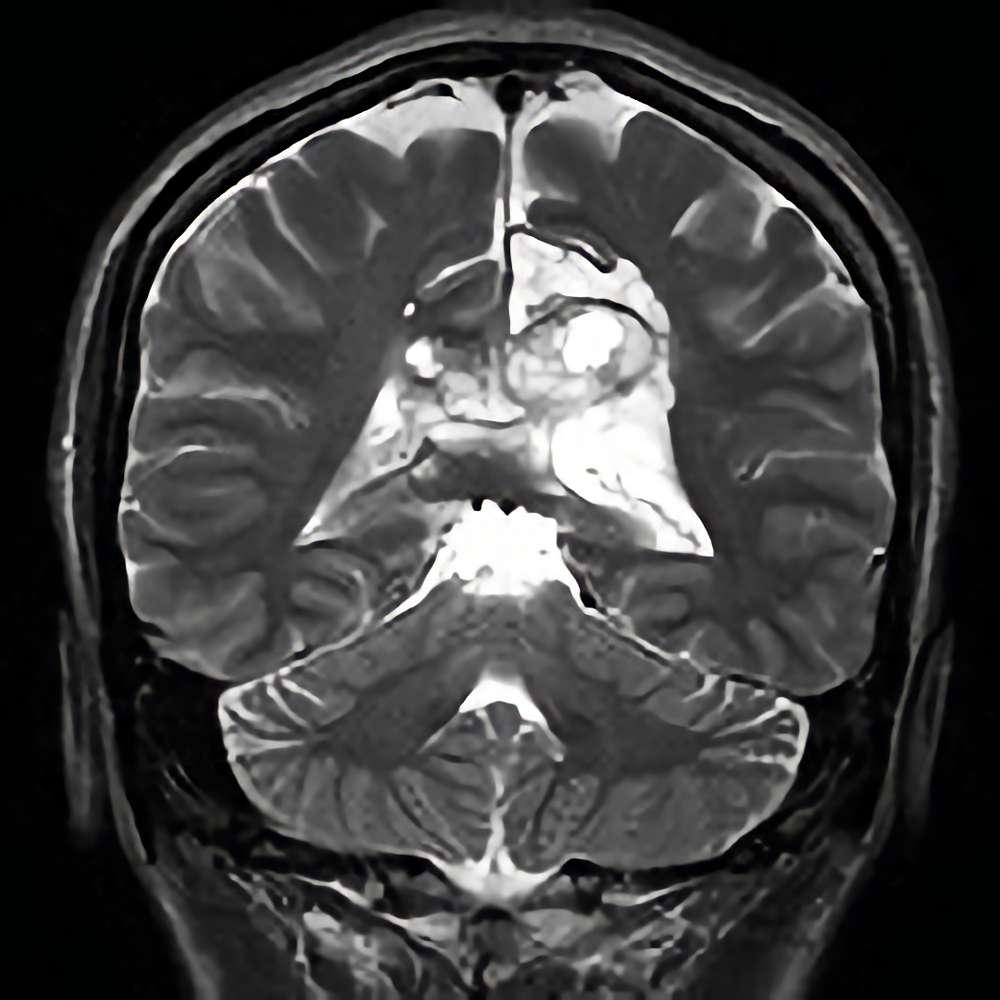

285

'22年4月

70代

膠芽腫

頭蓋内腫瘍摘出術

No.’22_42 手術前1

No.’22_42 手術前2

No.’22_42 摘出 前

No.’22_42  摘出 中

No.’22_42 摘出 後